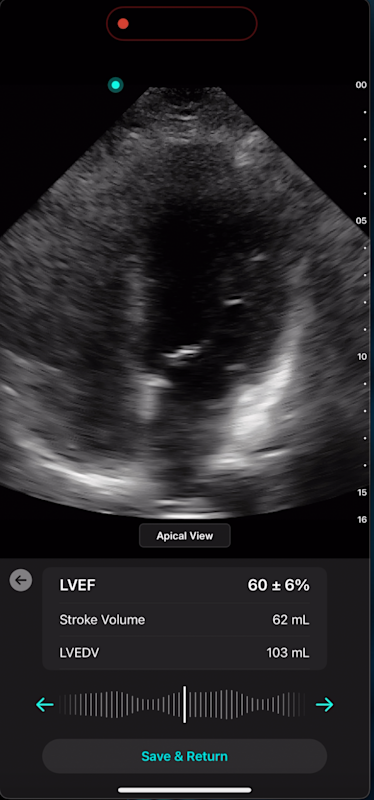

With Exo’s Cardiac AI, you can measure left ventricular ejection fraction (LVEF) and stroke volume in a few heartbeats in both parasternal long axis (PLAX) and apical four-chamber (A4C) views, making it easier than ever for POCUS users to get to answers.